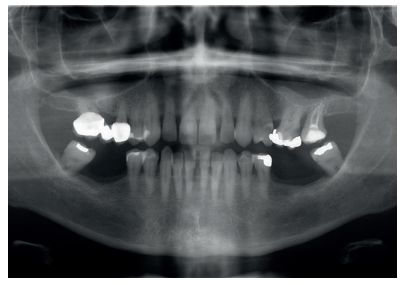

Paciente mujer de 55 años que acude a la consulta para rehabilitar protésicamente sectores posteriores (Figura 1). A nivel oral presenta patología dental y periodontal además de las ausencias de molares. Con necesidad de tratamiento quirúrgico, periodontal y restaurador (Figura 2).

A nivel general la paciente padece diabetes tipo II, hipertensión, hipotiroidismo, obesidad, ansiedad y déficit de vitamina D.

Todas estas patologías están bajo control médico y están en tratamiento con Enalapril, Semaglutida, Metformina, Empagliflozina, L-Tiroxina, Topiramato, Lorazepam, Fluoxetina y Calcidiol.

A nivel odontológico el diagnóstico y el tratamiento de la paciente presenta patología dental y periodontal además de las ausencias dentarias. Se realizaron obturaciones, tratamiento periodontal básico y quirúrgico, extracciones dentarias, rehabilitación con prótesis fija y tratamiento rehabilitador con implantes dentales (Figura 3).

A pesar de la múltiple patología general y tratamientos farmacológicos que presentaba la paciente que podrían haber condicionado la realización de alguno de estos procedimientos. Tras un estudio detallado de la situación general de la paciente y diversas interconsultas con su médico de atención primaria se concluyó que no había condicionantes generales que impidieran llevar a cabo nuestros tratamientos intraorales (Figura 4). El control médico de sus patologías, la monitorización de las variables clínicas y el estudio de la situación de la paciente permitió realizar todas las actividades de prevención, diagnóstico y tratamiento que necesitaba. Después de los tratamientos propuestos existen resultados objetivos de mejoría en su salud periodontal y se ha conseguido rehabilitar su función masticatoria.